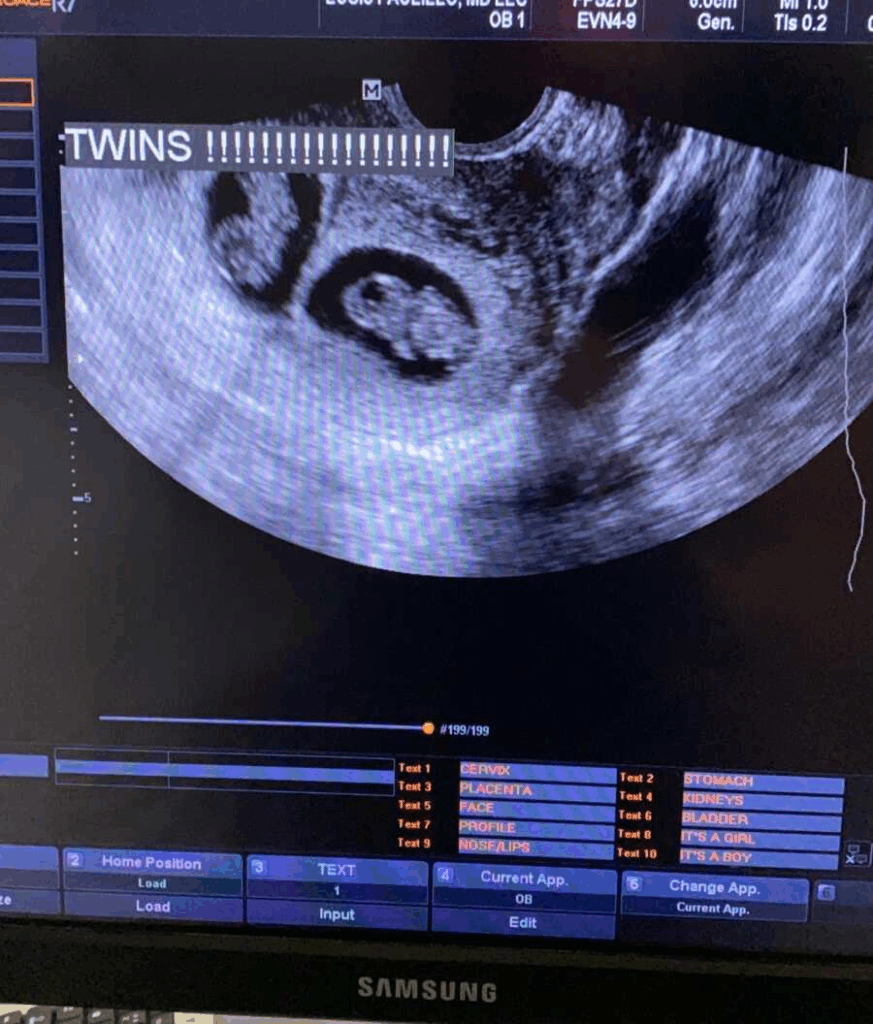

She smiled after a few minutes. “Good news. Our emotions are beating! I felt a wave of respite. She tossed the screen and said, “Here’s a baby… and here’s the second one!” Then the shock hit. twins. It was implausible to me. I never fictional that my grandmother’s prayers for twins would be replied.